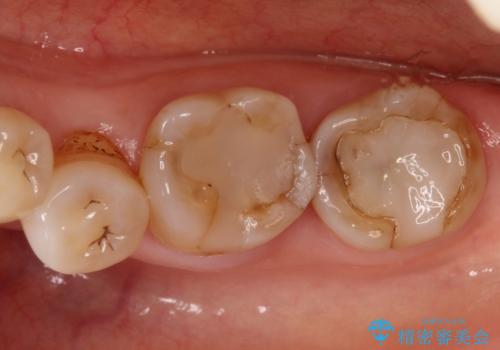

咬合が強く、歯牙にマイクロクラックが入っている状態でした。歯髄は保存可能と診断され、フルジルコニアクラウンによる治療を行いました。

咬合面に広範囲の修復物がある状態で中心に強い力が加わると歯牙は外方性の歪みが生じ、マイクロクラックができます。これを防ぐには、咬頭被覆するアンレー、もしくはクラウンによる治療が必要です。